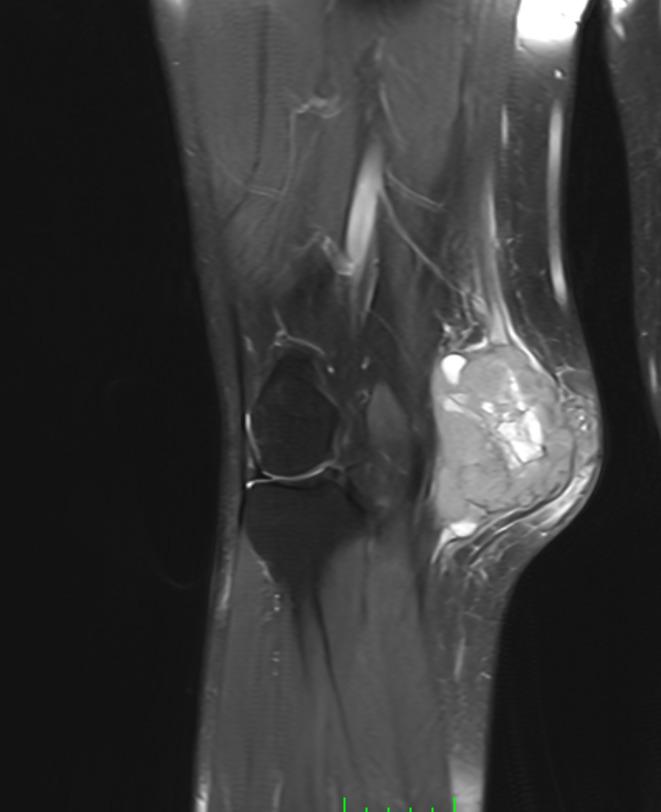

Muscle Cancer